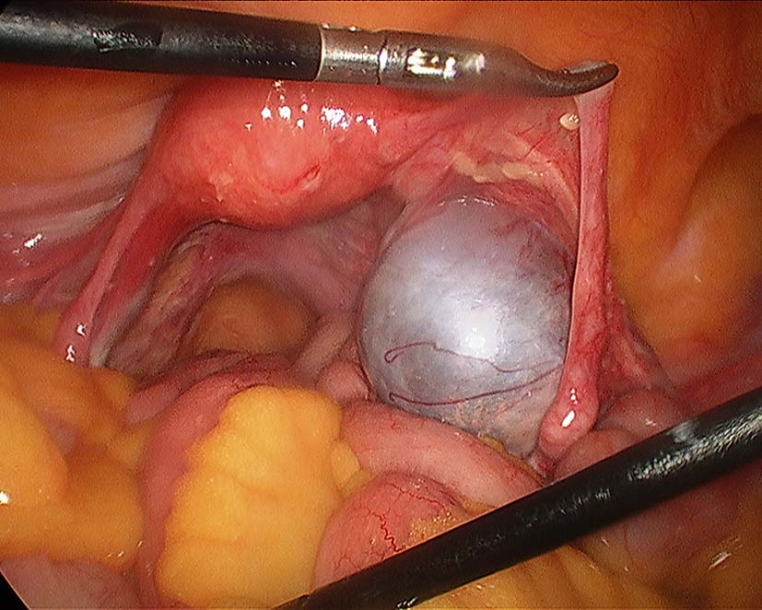

3.腹腔镜检查:是目前国际公认的内异症诊断的最佳方法,除了阴道或其他部位的直视可见的病变之外,腹腔镜检查是确诊盆腔内异症的标准方法。在腹腔镜下见到大体病理所述典型病灶或可疑病变进行活组织检查即可确诊。下列情况应首选腹腔镜检查:疑为内异症的不孕症患者,妇科检查及B型超声检查无阳性发现的慢性腹痛及痛经进行性加重者,有症状特别是血清CA125水平升高者。只有在腹腔镜检查或剖腹探查直视下才能确定内异症临床分期。

卵巢巧克力囊肿腹腔镜下表现